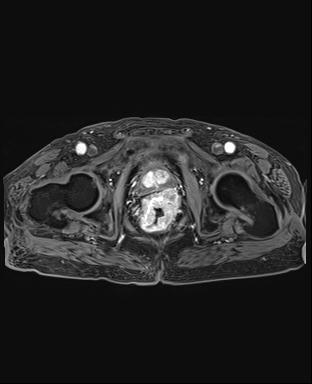

上圖為首發(fā)直腸癌患者,并有睪丸鞘膜積液。